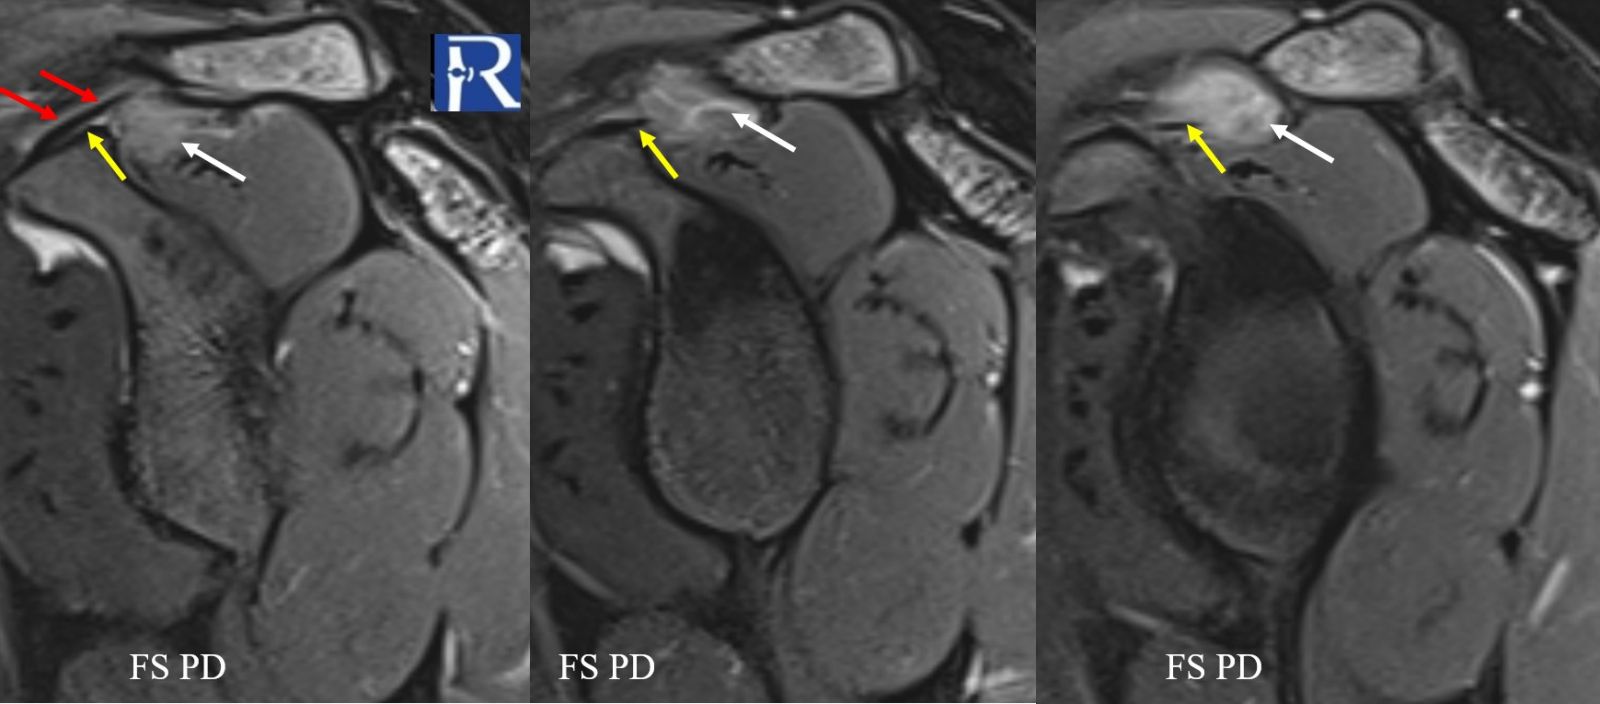

Location: Coracoclavicular space, adjacent to the supraspinatus tendon

- A well-defined solid soft-tissue mass located between the coracoclavicular and coracoacromial ligaments, immediately adjacent to the supraspinatus musculotendinous unit.

- The lesion is isointense to muscle on T1-weighted images.

- On fat-suppressed proton density sequences, the mass demonstrates intermediate to low signal intensity.

- On fluid-sensitive (fat-suppressed) sequences, the lesion again exhibits intermediate-to-low signal, suggestive of hemosiderin or cellular lesion.